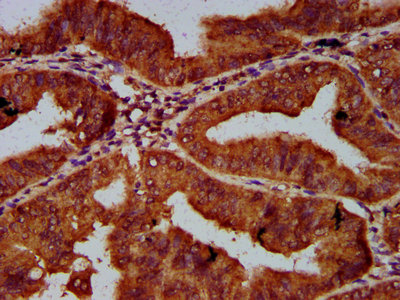

IHC image of CSB-PA617942LA01HU diluted at 1:600 and staining in paraffin-embedded human endometrial cancer performed on a Leica BondTM system. After dewaxing and hydration, antigen retrieval was mediated by high pressure in a citrate buffer (pH 6.0). Section was blocked with 10% normal goat serum 30min at RT. Then primary antibody (1% BSA) was incubated at 4°C overnight. The primary is detected by a biotinylated secondary antibody and visualized using an HRP conjugated SP system.

IHC image of CSB-PA617942LA01HU diluted at 1:600 and staining in paraffin-embedded human liver cancer performed on a Leica BondTM system. After dewaxing and hydration, antigen retrieval was mediated by high pressure in a citrate buffer (pH 6.0). Section was blocked with 10% normal goat serum 30min at RT. Then primary antibody (1% BSA) was incubated at 4°C overnight. The primary is detected by a biotinylated secondary antibody and visualized using an HRP conjugated SP system.